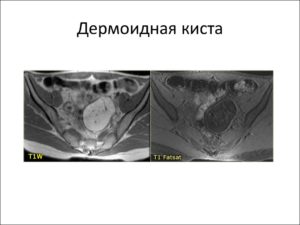

Дермоидная киста малого таза

Дермоидная киста яичника – дополнительное образование овариальной ткани, состоящее из толстостенной капсулы, внутри которой содержится слизеобразная масса с различными включениями (кожей, жировой тканью, сальными железами, волосами, костями, зубами, нервной тканью).

Клинически дермоидная киста яичника проявляет себя при достижении больших размеров: в этом случае могут отмечаться боли в животе и пояснице, дизурические нарушения, расстройства дефекации. Дермоидные кисты склонны к воспалению, нередко наблюдается перекрут ножки кисты. Диагностика включает гинекологический осмотр, УЗИ, МРТ, лапароскопию.

Лечение дермоидных кист яичника оперативное – кистэктомия, клиновидная резекция яичника или овариоэктомия.

Дермоидная киста (дермоид, зрелая тератома) – доброкачественная опухоль яичника, которая встречается у 15-20% женщин с овариальными кистами.

Дермоидная киста яичника обычно имеет круглую или овальную форму, гладкие наружные стенки, может вырастать диаметром до 15 сантиметров.

Внутри полость тератомы выстлана многослойным эпителием и заполнена желеобразным содержимым со зрелыми фрагментами производных эктодермы, эндодермы и мезодермы (сальных и потовых желез, волос, жировой, нервной, костной и др. тканей).

- дермоидная киста. Киста, которая содержит волосы, волосяные фолликулы и сальные железы